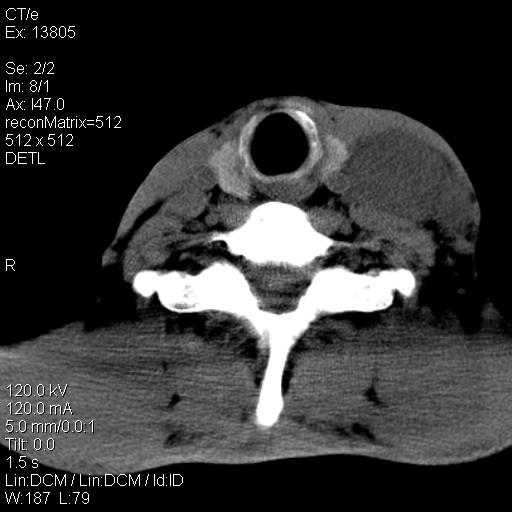

上腹部疼痛一月,呕吐10天,发现左侧颈部包快10天 胸部cr片未见明显异常。

左侧胸锁乳突肌下方、颈血管旁低密度肿块影,肿块密度尚均匀,边缘大部分清楚,邻近组织稍受压移位。考虑颈部神经鞘瘤可能性大。

颈部及腹膜后淋巴瘤可能性大